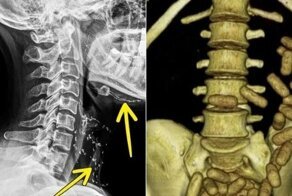

2. А это самый большой почечный камень

Его удалили из жителя Венгрии. В длину камень был около 17 см, вес составлял 1 кг.